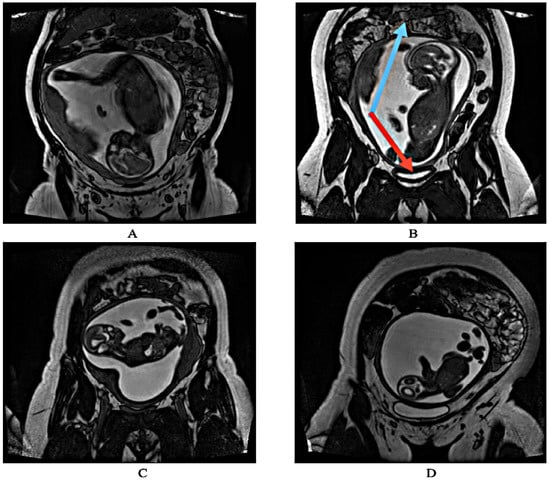

1. Introduction

2.1. Dataset